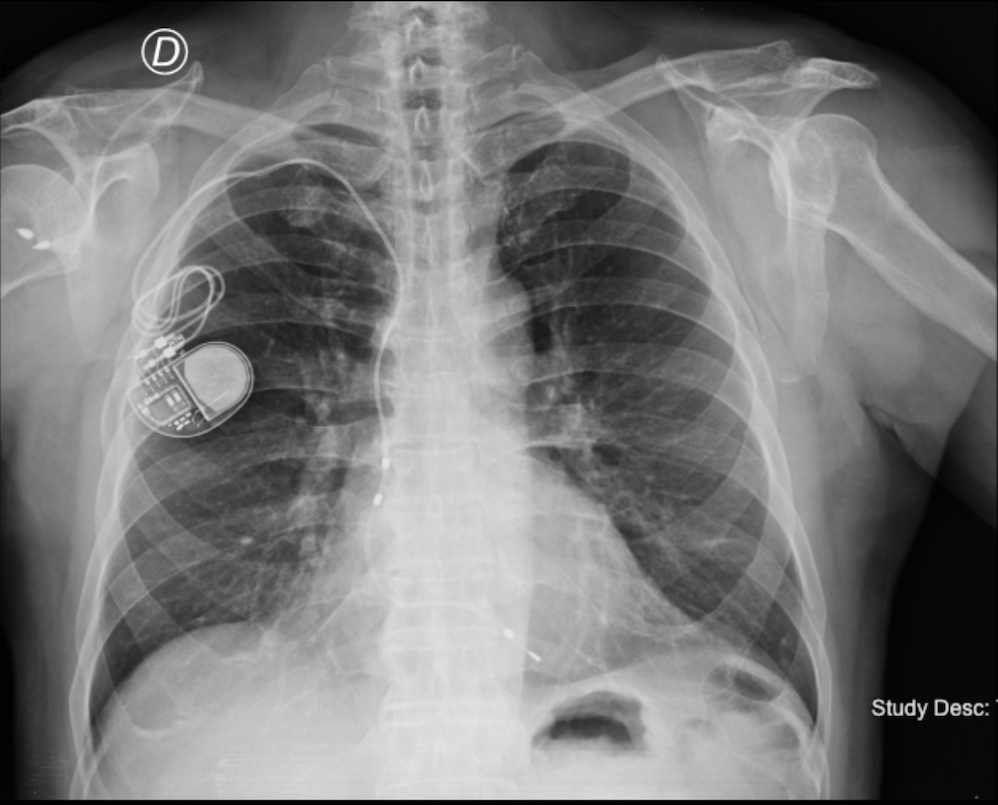

Introducción: Las indicaciones de ablación con sistema tridimensional en pacie...

Introducción: La ablación de arritmias en la edad pediátrica es un procedimie...